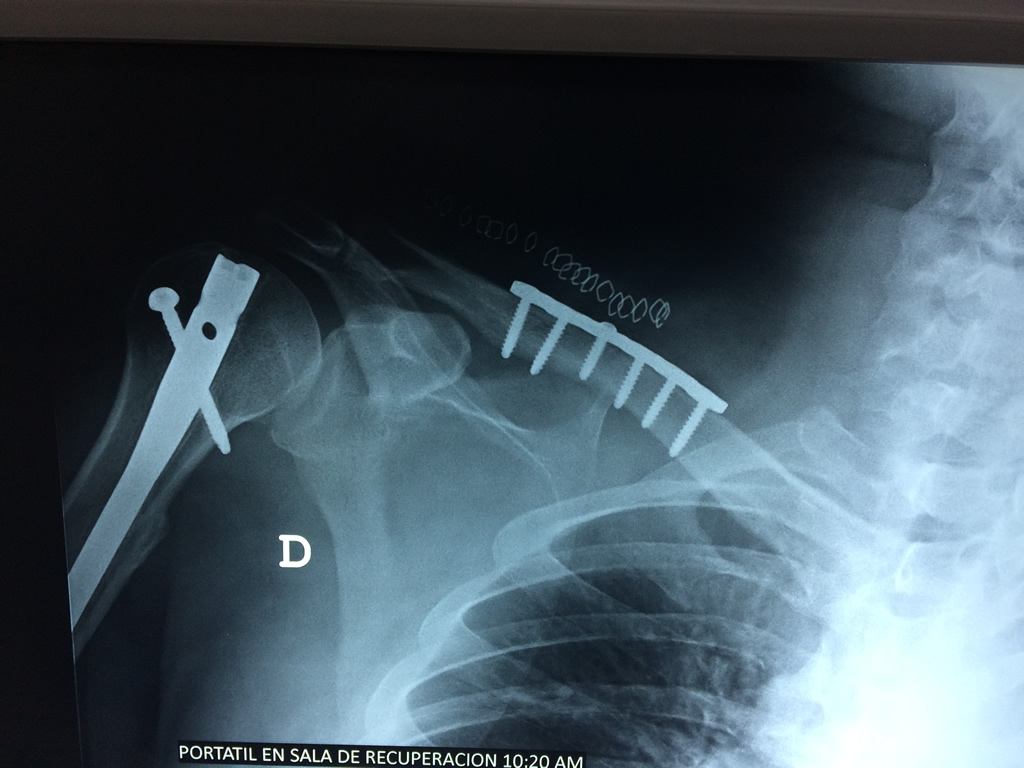

La clavícula es un hueso largo, con forma de "S" itálica, situado en la parte anterosuperior del tórax. Junto con la escápula forman la cintura escapular. Se puede palpar por toda su longitud y se extiende del esternón al acromion de la escápula, siguiendo una dirección oblicua lateral y posterior.